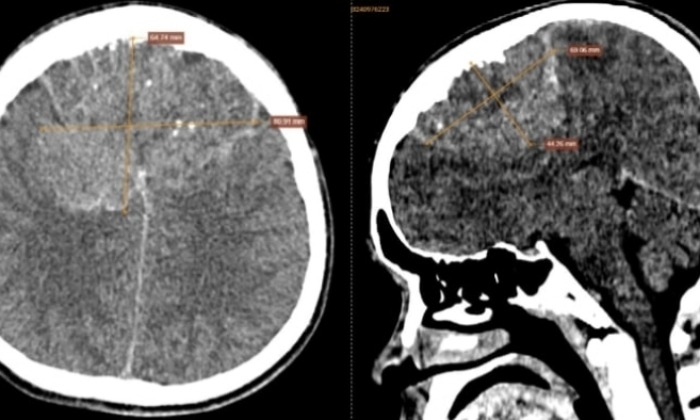

Sau khi đi khám tại cơ sở y tế địa phương, anh được chỉ định chụp CT sọ não không tiêm thuốc cản quang. Kết quả chụp cho thấy một khối bất thường vùng trán sát bản xương sọ, có dạng mô mềm, bờ không đều, ranh giới rõ ràng nhưng kèm phù não nhẹ. Bên trong khối u xuất hiện nhiều nốt vôi hóa và ổ hoại tử, kích thước lên tới 80 x 65 x 55 mm.

Kết quả ghi nhận: vùng trán sát bản xương sọ xuất hiện khối tổn thương tỷ trọng mô mềm, bờ không đều, có phần bờ dạng thùy múi, ranh giới tương đối rõ. Quanh tổn thương có phù não nhẹ ở nhu mô bờ dưới, nghi ngờ xâm lấn nhu mô não vùng trán - đỉnh phải. Bên trong khối ghi nhận nhiều nốt vôi hóa, kèm vài ổ giảm tỷ trọng dạng hoại tử. Kích thước tổn thương đo được khoảng 80 x 65 x 55 mm.